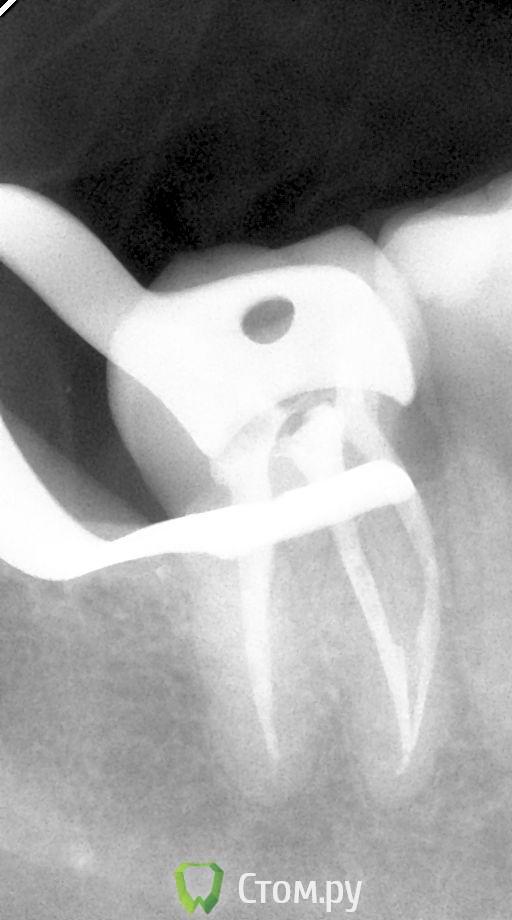

Каплан Опубликовано 25 ноября, 2011 Поделиться Опубликовано 25 ноября, 2011 не путайте. ЭДТА может быть разной концентрации. Одна, в составе таких препаратов как RC-prep, применяется для расширения каналов. Другая (кажется, 17%) применяется при финишной обработке канала для удаления смазанного слоя. Ее-то и заменяют лимонкойRC-Prep - это 15% гель ЭДТА. как бы 2 процента тут погоду думаю не сильно меняют, вопрос в "форме" - жидтким мыть легче... Насчет того сколько отступать - зависит от системы, и формы канала. нет одного рецепта...Как пример, померил по ап.лок, отнял 1 мм, и до 30.06 М2, потом еще раз померил, и на выходе получил упор не на 1 мм меньше, а на 0,5 мм, чем изначально. А планировал 0,5 мм ручками доработать под контролем ап.лок. пришлось финишировать на этой длине 35.02. http://s017.radikal.ru/i424/1111/8b/2c06a0a1f25et.jpgесть исследования по изменению рабочей длины для некоторых эндо-систем.. (для протейперов и профайлов точно есть. еще кажется К3). там вообще оч интересные циферки... Ссылка на комментарий